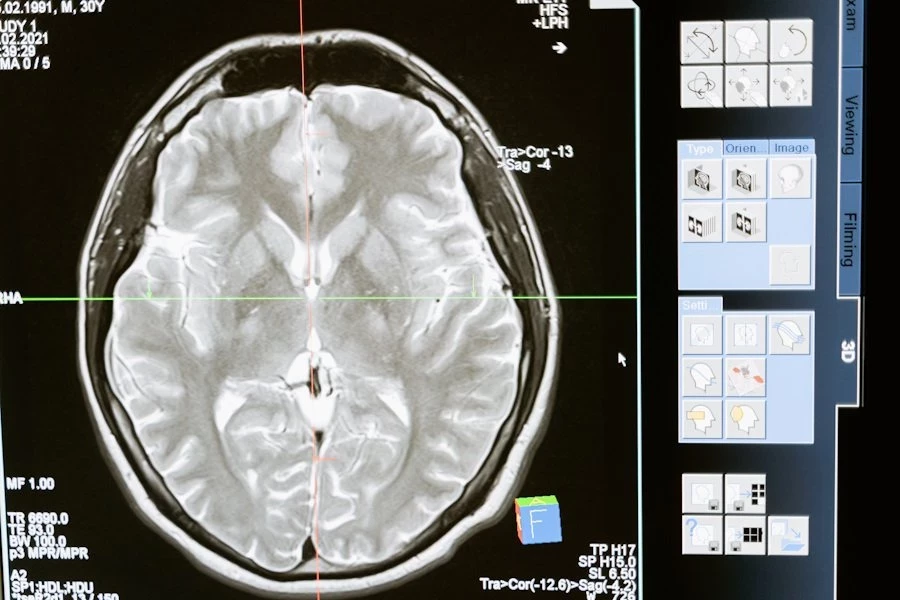

Ученые выявили 32 белка, регуляция которых в возрасте от 45 до 60 лет была сильно связана с возможностью развития деменции в пожилом возрасте. Некоторые из этих белков играют важную роль в мозге, но большинство выполняют другие функции в организме.

Особый интерес вызвали белки, связанные с процессом протеостаза — это контролирующий механизм, который балансирует уровень белков в организме. Этот механизм важен для предотвращения скопления белков в мозге, что часто наблюдается у людей с болезнью Альцгеймера, наиболее распространенным видом деменции.